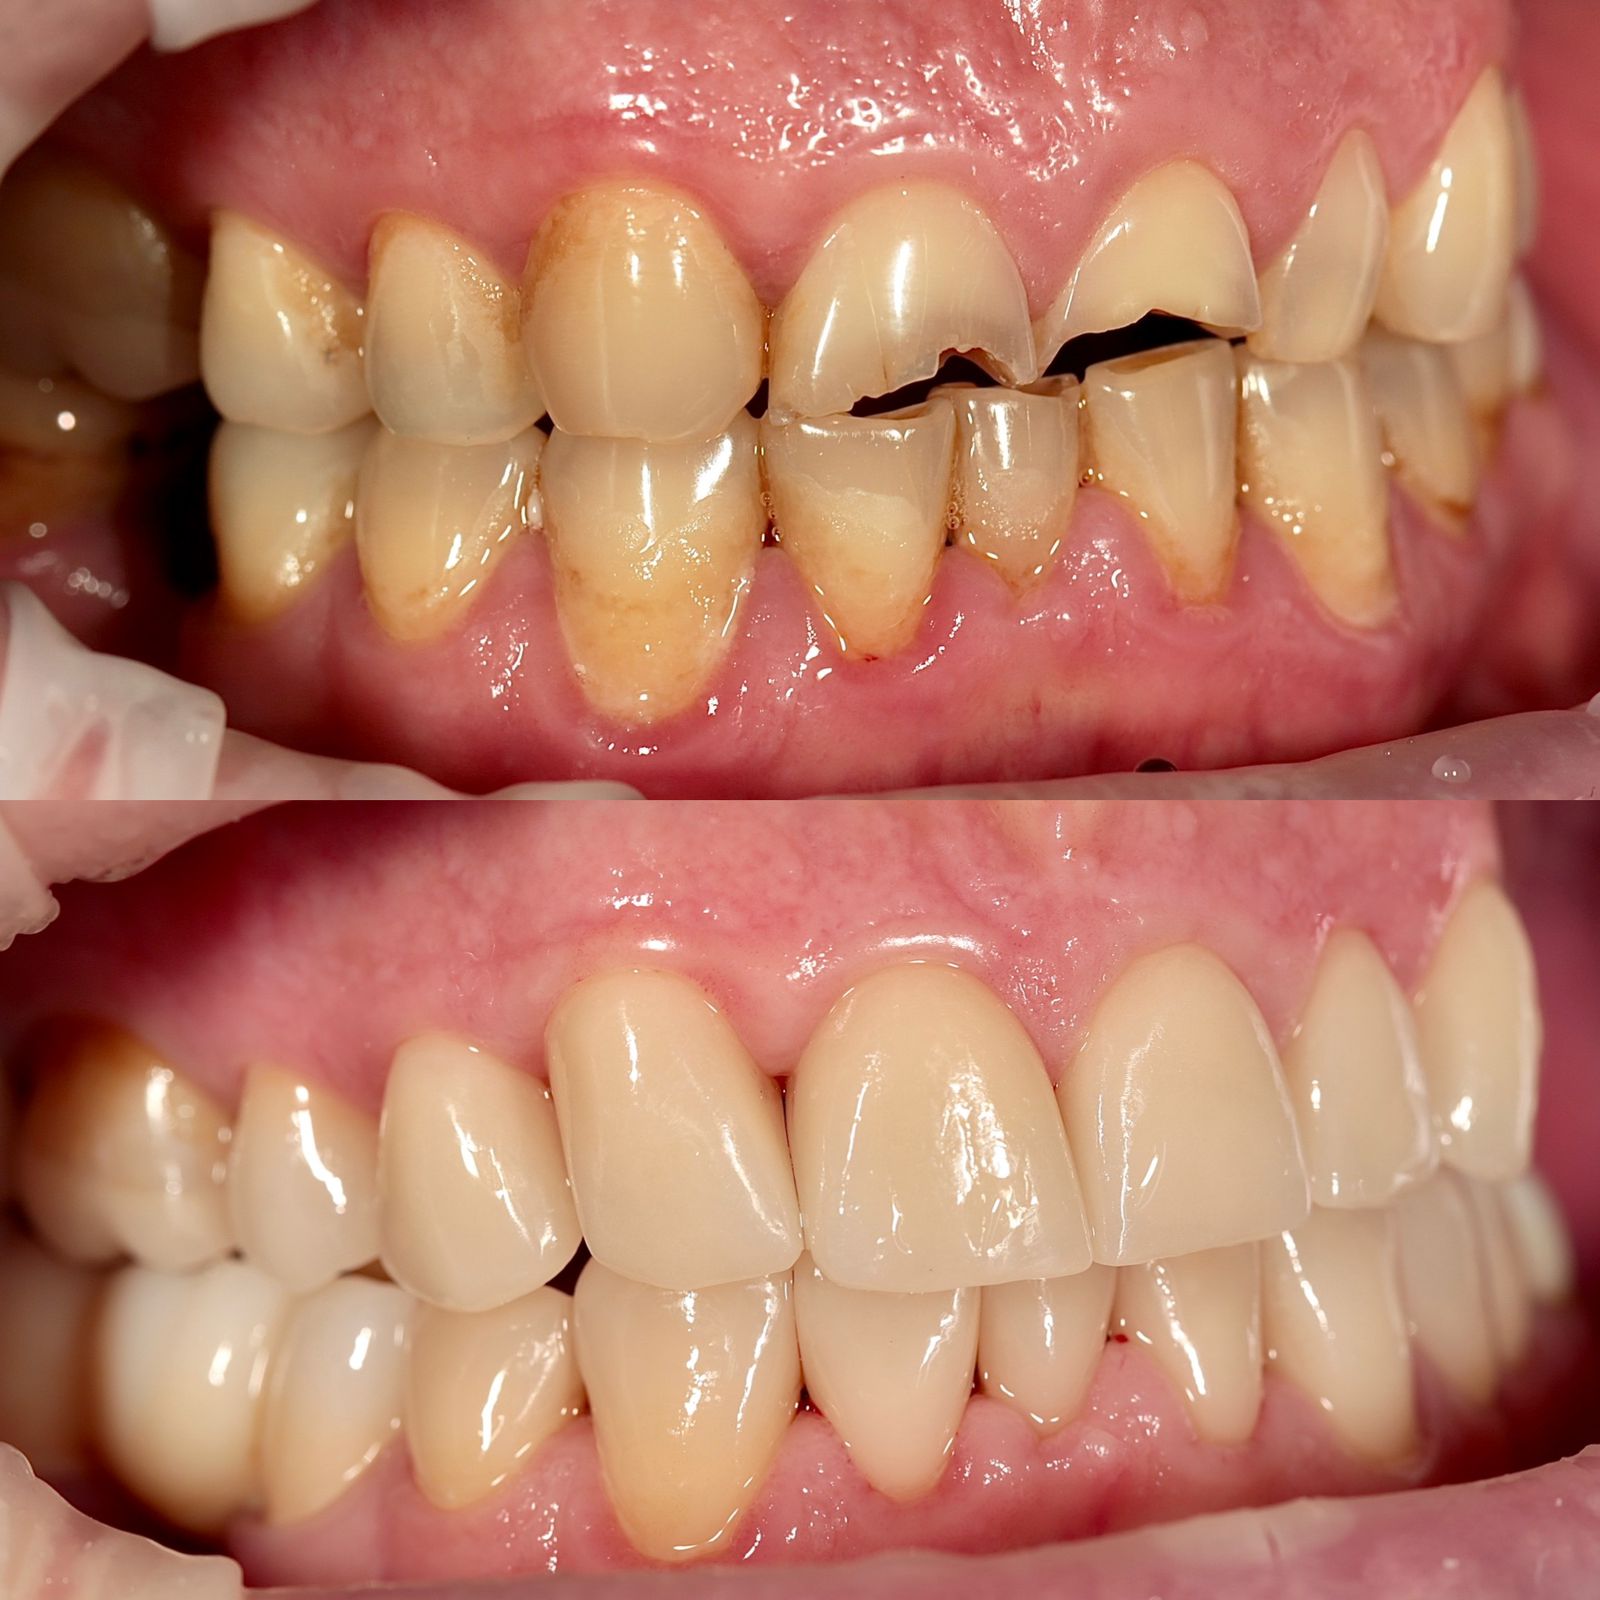

Циркониевые коронки на имплантах

На временных коронка проверена высота прикуса и окклюзия.

Установлены коронки из оксида циркония с опорой на импланты и керамические виниры на нижних фронтальных зубах.